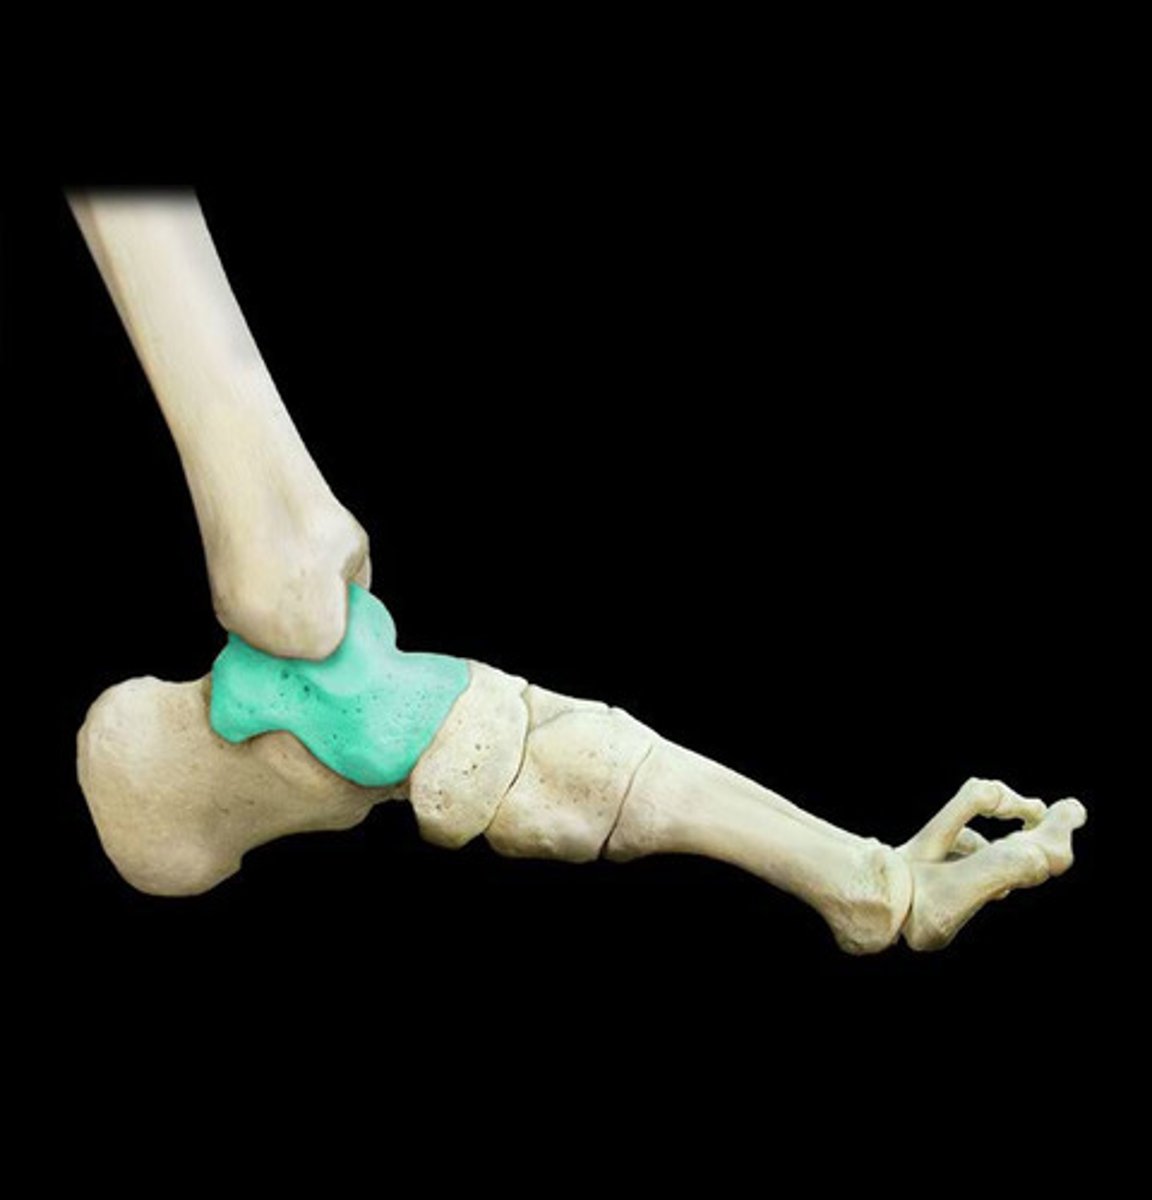

In the talocrural joint, is the talus the convex or concave component?

Talus is CONVEX in the talocrural joint

What is the concave component of the talocrural joint?

The tibia and fibula

What type of joint is the talocrural joint? (specific classification based on shape)

Mortise joint